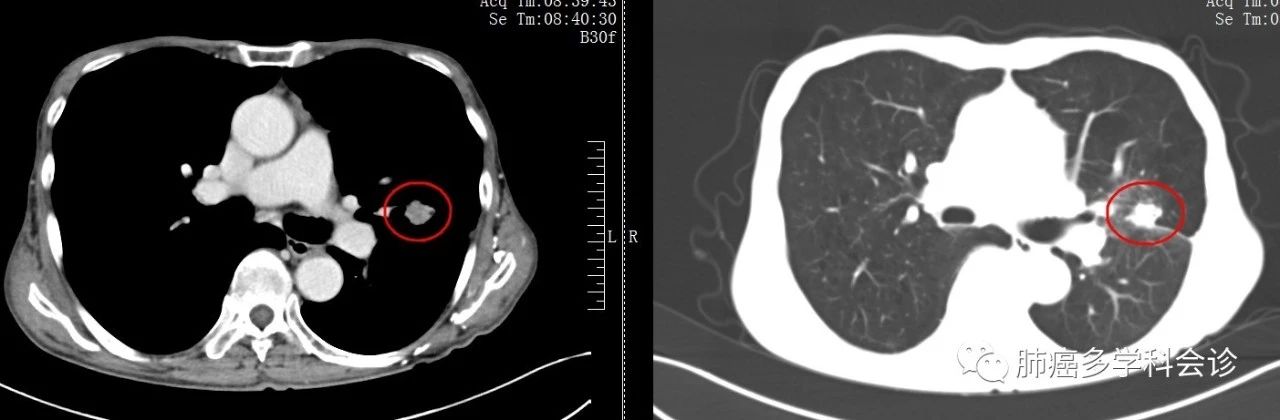

患者赵*,男,80岁,2017年2月体检时发现:右肺有一个24×21mm不规则肿块。

活检病理:肺腺癌

基因检测:EGFR 21外显子 L858R突变

PET-CT:右肺上叶软组织代谢活跃,符合肺癌。其它处未见转移征象

疾病临床分期:cT1bN0M0,ⅠA期。